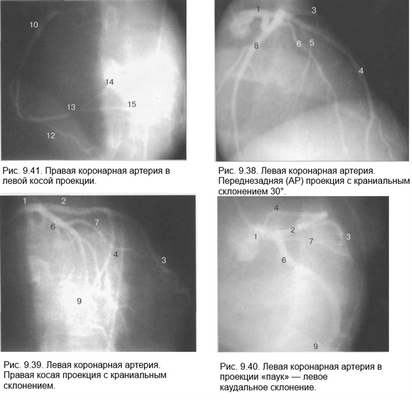

Рис. 9.37. Левая коронарная артерия. Правая косая проекция.

Здесь и на рис. 9.38—9.46:

1 — левая коронарная артерия; 2 — проксимальная треть передней нисходящей артерии; 3 — первая диагональная ветвь передней нисходящей артерии; 4 — дистальная часть передней нисходящей артерии; 5 — септальная ветвь передней нисходящей артерии; 6 — проксимальная часть огибающей артерии; 7 — первая маргинальная ветвь огибающей артерии; 8 — промежуточная артерия; 9 — дистальная часть огибающей артерии; 10 — проксимальная часть правой коронарной артерии; 11 — ветвь синусного узла правой коронарной артерии; 12 — ветвь острого края правой коронарной артерии; 13 — бифуркация правой коронарной артерии; 14 — правая левожелудочковая ветвь правой коронарной артерии; 15 — задняя нисходящая ветвь правой коронарной артерии.

Фиксация изображения коронарных артерий производится последовательно в нескольких плоскостях.

На рис. 9.37—9.41 изображены левая и правая коронарные артерии и их ветви при равномерном типе коронарного кровообращения в обычной последовательности проекций.